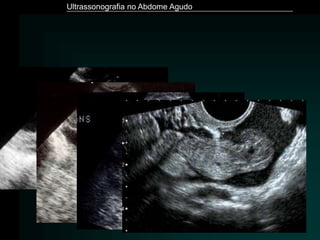

Apendicite Aguda

Ultrassonografia no Abdome Agudo

Rybkin. Radiol Clin N Am 45 (2007) 411–422

Puylaert. Radiol Clin North Am. 2003 Nov;41(6):1227-42